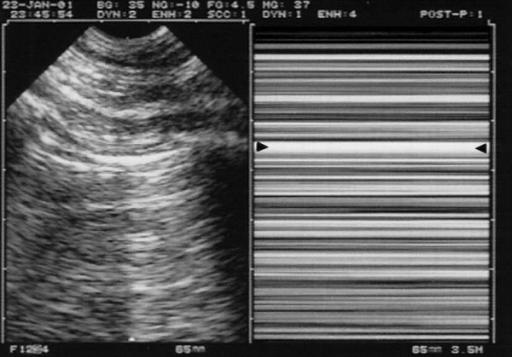

The opposition of pleural and aerated lung below it produces a characteristic image as the parietal and visceral pleura slide against each other, often described as “marching ants”. An M-mode spike through the intercostal window will produce another characteristic temporal image known as the “seashore sign”.

In the setting of pneumothorax, the M-mode image will become a “barcode sign”. This view is less valuable in the identification of haemothorax or other intrapleural free fluid, they are probably better looked for at the diaphragm in the RUQ and LUQ views.

Right: M-mode, the abolition of lung sliding is visible as the “Barcode sign”. The arrows indicate the pleural signal. Lichtenstein DA - CC-BY 3.0 Link